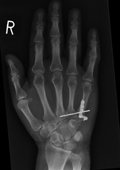

Im Zentrum für Orthopädie und Unfallchirurgie werden sämtliche Frakturen der Hand und des Handgelenks nach aktuellen Therapiealgorhythmen behandelt. Neben der gesamten Bandbreite der konservativen, nicht operativen Behandlungsmaßnahmen werden alle operativen Bruchstabilisierungen mittels aktueller Verfahren und Implantate versorgt.